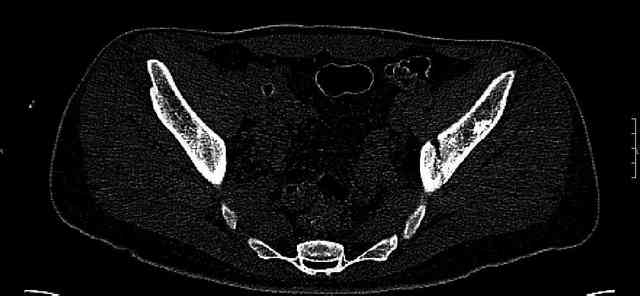

The last two images from the 3-D CT scan certainly makes the fracture look worse than the plan radiographs.

While not claiming to have the best 3D brain around, it appears to me from the limited images available, that the caudal segment is stable from the symphysis to the SI joint on the fracture side. I would love to see the rest of the transverse CT images to see where the fracture line actually exits posteriorly on both the inner and outer tables of the ilium. In my hands,

Some more images. Does it help to guess which part of the acetabulum is displaced?

Normal appearing SI joints and a healed posterior column limb... my bet's on caudal segment displacement.